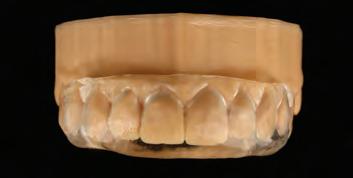

A diagnostic wax-up is frequently employed to facilitate the planning phase in restorative dentistry. Diagnostic waxups can be created both analog and digitally. Wax can be added to change the morphology of the teeth to simulate

the proposed esthetic and function.18,19 However, with the advancement of dentistry, digital wax-ups have become increasingly popular.20 This process involves scanning a patient’s mouth or a stone model, altering the virtual shape of their teeth using computer software, and then 3D printing the replica.21 Once the wax-up is completed, it is presented to the patient and utilized to create mock-ups before the final procedure.22 This helps to understand better and manage patient’s expectations and gives them a sneak peek at how the restorations would look in person.8,22 Wax-ups can fabricate silicone indexes to guide the desired anatomy and obtain proper tooth width proportions,21 as shown in Figure 1. A restorative plan is then formulated using direct or indirect techniques.

Fig. 1a: STL of maxilla arch. Fig. 1b: Digital wax-up will facilitate the planning phase.